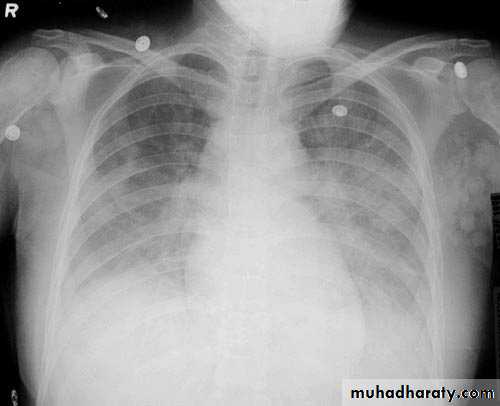

Lobar consolidation

Where increased density/opacity is seen in individual lung lobes. Sharp delineation can be seen when consolidation reaches a fissure, since it does not cross. Air bronchograms can also be seen due to bronchi becoming visible against the dense diseased tissue. Volume loss is usually not seen..

Right upper lobe consolidation

RUL consolidation will be seen as an increased opacity within the right upper lobe. Opacity may be sharply bordered by the horizontal fissureSome loss of outline of the upper right heart border may be apparent

Dense opacity seen above the horizontal fissure.

Air-bronchogram line

The lower border of the consolidation is sharply delinated by the horizontal fissure suggesting it lies in the anterior segment of the RUL